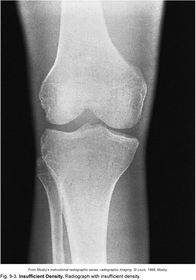

Insufficient Density image appears too bright (too many x-ray photons)

Density the quantity of photons reaching the IR